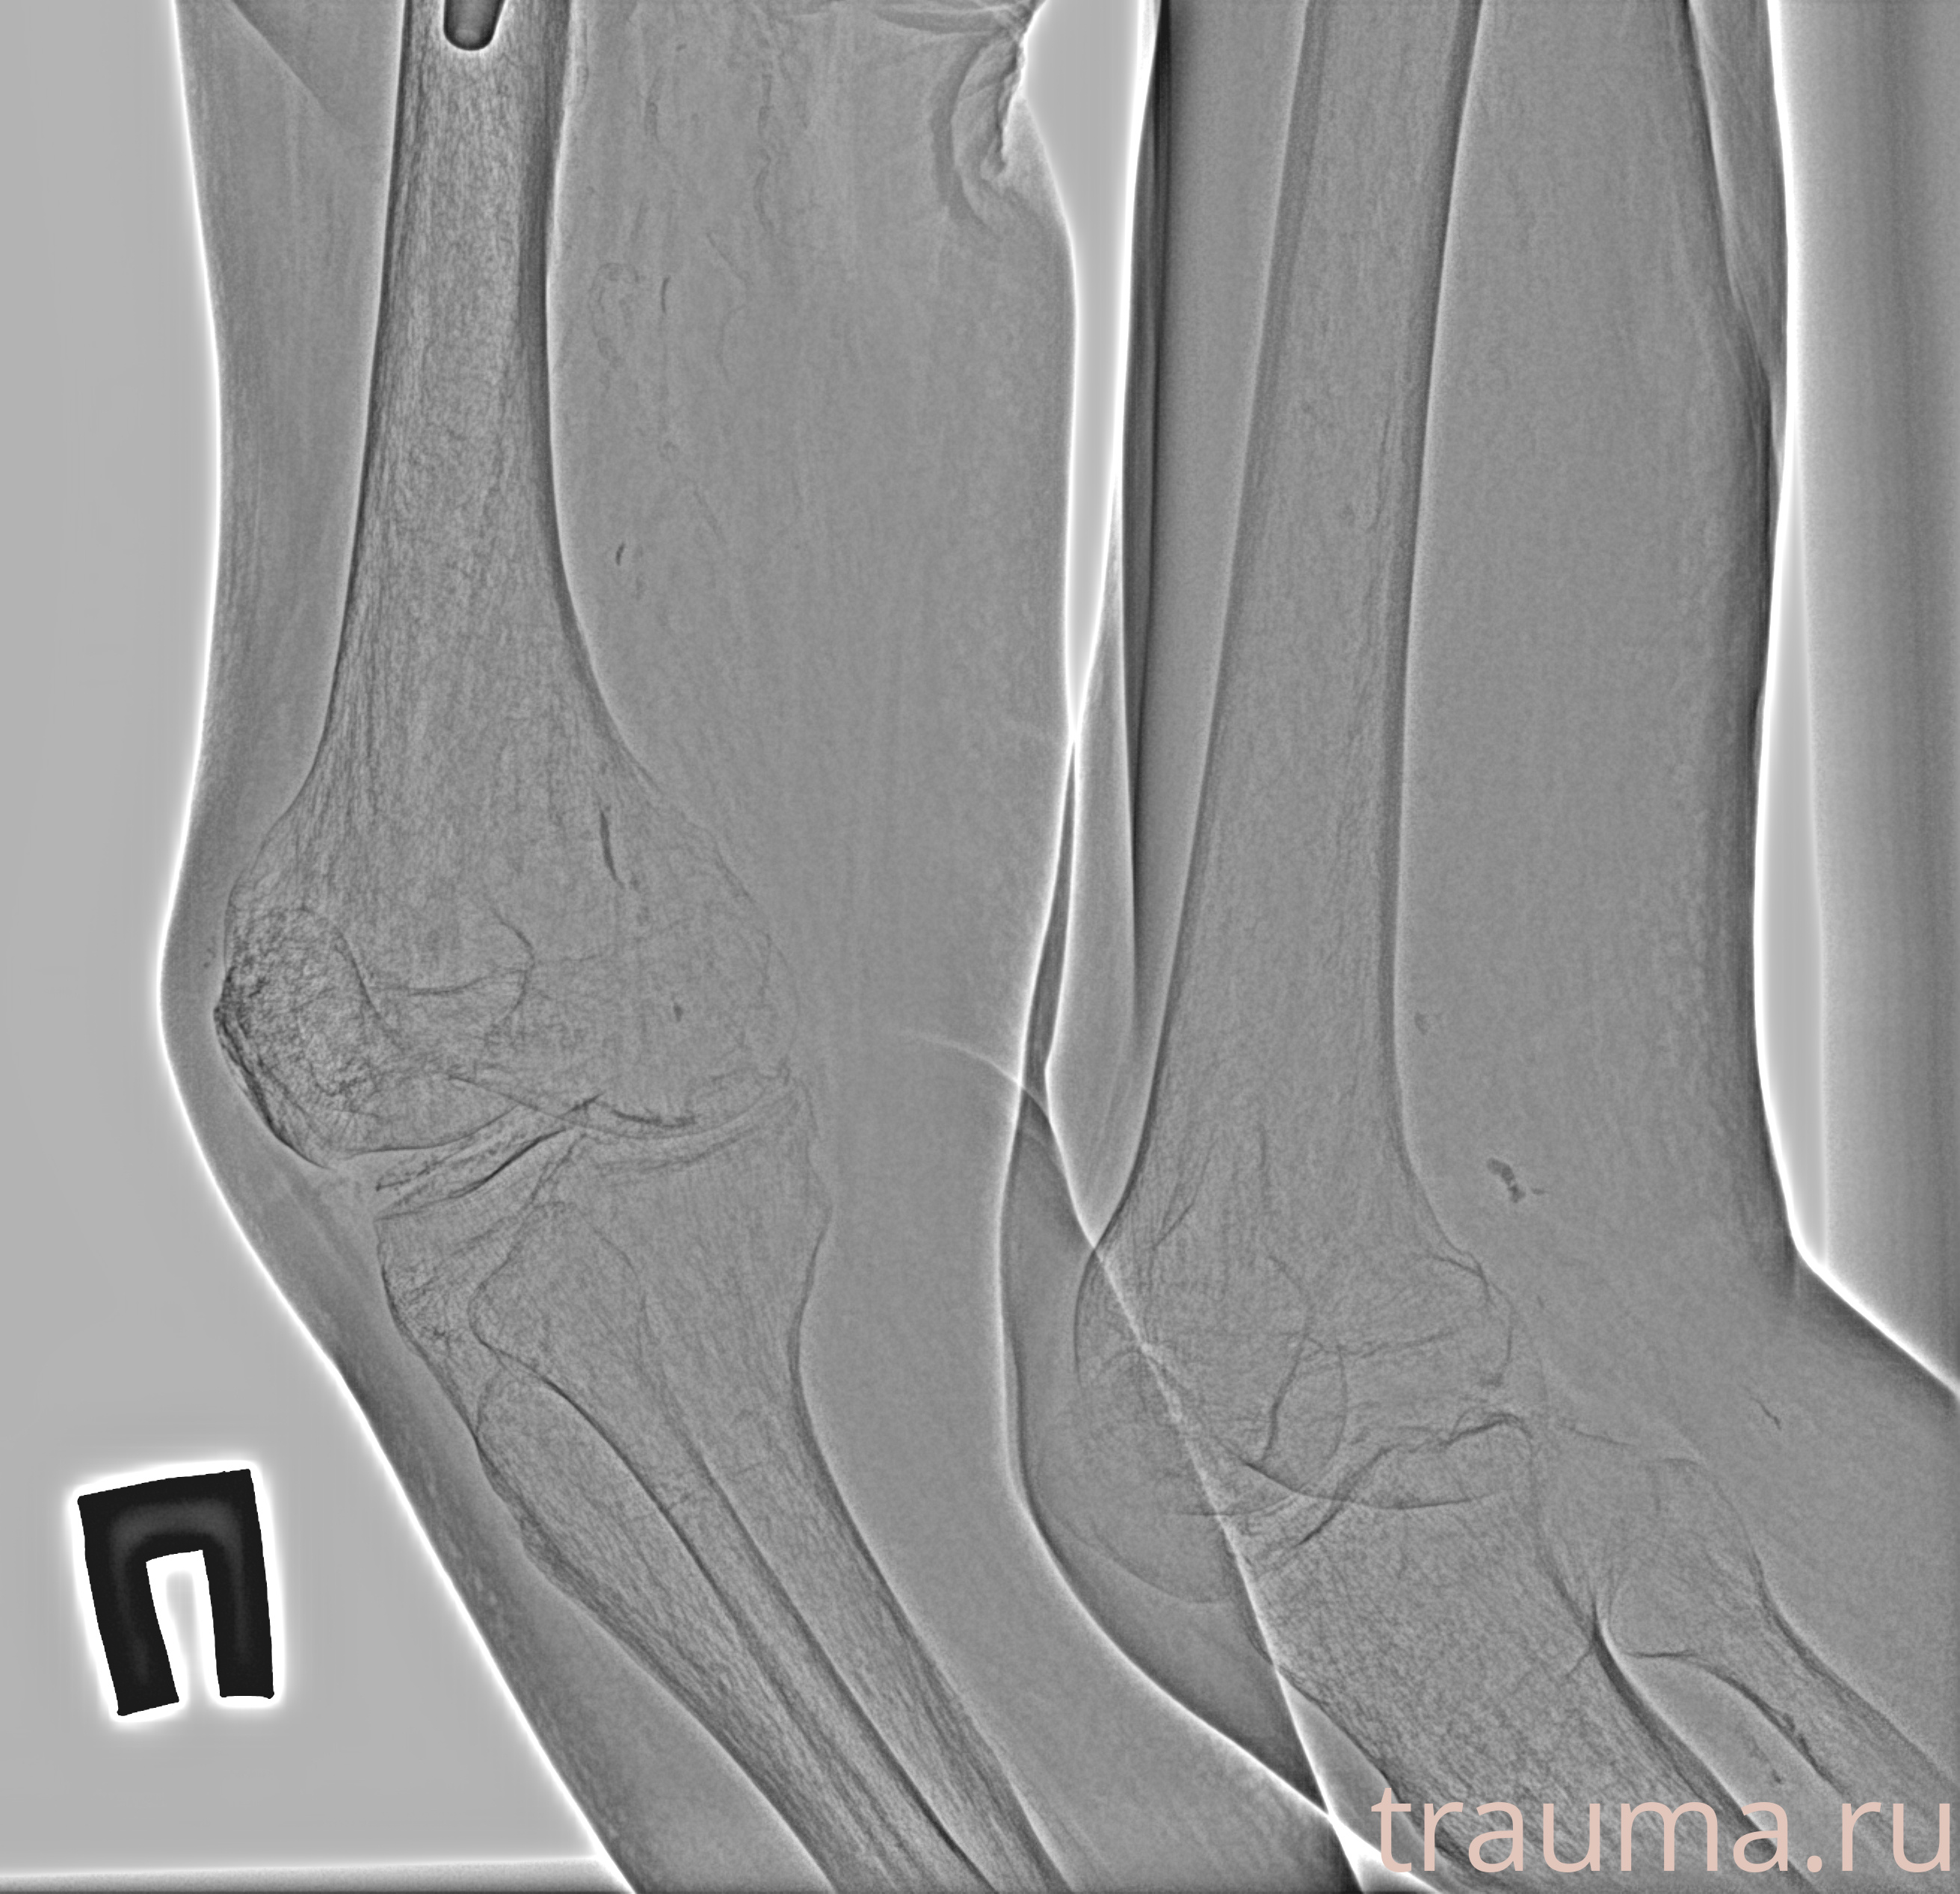

Рентгенограммы

Рентген на дому: по вашему адресу приезжает врач-рентгенолог, травматолог-ортопед с мобильным рентгеновским аппаратом, проводит диагностику травмы или заболевания, делает необходимые рентгенограммы, дает рекомендации по дальнейшему лечению. Получить качественные снимки в домашних условиях возможно благодаря уникальной методике, разработанной МосРентген Центром для института  Склифосовского